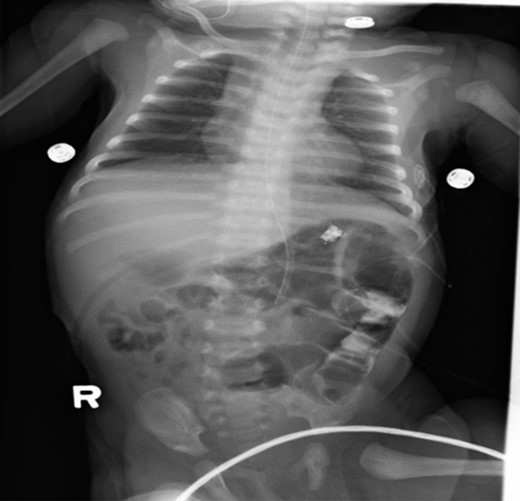

Postoperative care included monitoring in neonatal intensive care unit. Upper GI series (Figs 3 and 4) demonstrated no evidence of leakage. The patient tolerated a trial of pedialyte feedings and was subsequently discharged home.

Post-operative abdominal x-ray showing gas throughout the bowel and residual contrast in the descending colon.